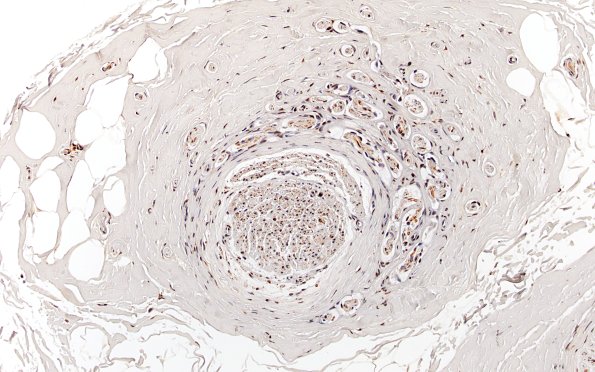

Washington University Experience | PERIPHERAL NEUROPATHY | 19 TRAUMATIC INJURIES | 10B1 Neuroma (Case 10) NF 20X

10B1,2 These sections show the mini-fascicles contain axons and also demonstrate diminished numbers of axons in the adjacent intact-appearing fascicle. (NF IHC)